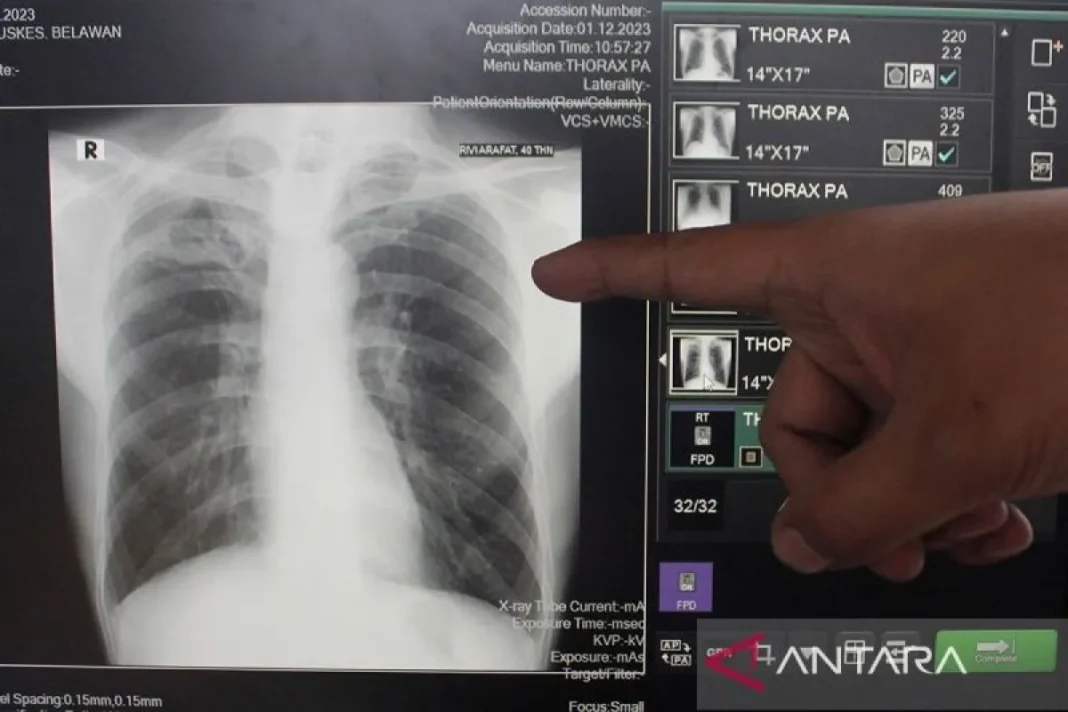

Dia menyebutkan, terdapat sejumlah inisiatif untuk menyukseskan inisiatif itu, antara lain penggunaan X-ray dan program Cek Kesehatan Gratis (CKG) untuk memasifkan penemuan kasus secara aktif (active case finding).